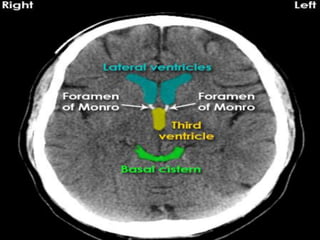

• Ventricles symmetry and cisterns any

effacement.

Approach to theCT • Look parenchyma for hypodensities ,hyperdensities, their location, shape, homogenous/heterogenous,any mass effect or odema. • Grey-white matter differentiation, any enhacement if contrast film. • Ventricles symmetry and cisterns any effacement.